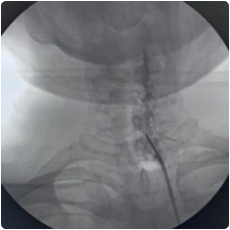

image 910

Intraop fluoroscopy image of needle placement at the cervical facet